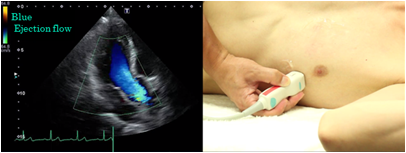

Color Doppler method

With the color Doppler method, blood flow towards the probe is displayed red, the flow away from the probe is displayed blue: the brighter the hue, the faster the relative velocity. For gain adjustment of color Doppler imaging, you should raise the gain until noise appears and then decrease it until the noise disappears to make observations and recordings. Adjust without widening the color display area more than necessary because the frame rate is reduced and real time performance falls when it is adjusted too wide.

Left ventricular ejection flow pattern

As in case of the left ventricular inflow pattern, you must try your best to set a view in which the Doppler beam is in parallel with the ejection flow pattern to record the left ventricular ejection flow pattern. The position of the sample volume is set at the center of the left ventricular outflow tract just below the aortic valve.